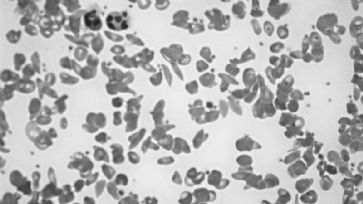

Was ist wohl gefährlicher: Die Grillwurst oder das multiresitente Chyseobacterium indologenes? /

Doch keiner merkt es. Deshalb fiel auch niemanden auf, dass Barack Obama mit seinem Entscheid, den Amerikanern eine Gesundheitsvorsorge zu verordnen statt die Banken zu regulieren, langfristig mehr Menschen krankgemacht, ja getötet haben wird, als wenn dies grad andersrum gelaufen wäre. Die WHO betreibt seit Jahrzehnten Ideologie statt Gesundheitspolitik. Deshalb erklärt sie nur die Wurst zum Krebs, aber nicht die Wurstindustrie. Dabei ist der Zusammenhang für alle klar, die sich auch nur einen Tag lang mit der industriellen Herstellung, Verbreitung und Werbung von Fleisch auseinandersetzen. Wer lebende Tiere wie tote behandelt, braucht Tausende Tonnen Antibiotika, um doch noch das Fleisch herzustellen, das seinen Namen nicht mehr verdient. Der Billigfleischpreis wird dann durch Multiresistenzen quersubventioniert, ohne dass dies die verdammten Agrarlobbyisten oder WHO-Spezialisten wirklich medienerregend aufzeigen würden. Wurst ist krebserregend? Ein Klacks gegen die tausenden von Menschen, die wegen diesen Multiresistenzen sterben. Wurst ist krebsfördernd? Ja klar! Denn die Billigwurst wird von einer Lebensmittelbranche produziert, die mit diversen Zusatzstoffen mittlerweile locker Gammelfleisch, Teigtaschen aus geschreddertem Karton oder Klärschlammgemüse schmackhaft machen kann und diese auch locker verkauft. #Wurstgate ist lustig. Und wenn es dazu führt, dass einige Schweine, Kälber, Rinder und Hühner weniger in ihrem Kot ersticken, in Enge, Dunkelheit und Tortur verelenden, dann hat die WHO einen Preis verdient. Mit Gesundheit hat dies wiederum nichts zu tun, aber mit der Würde von Lebewesen. Ginge es der WHO aber wirklich um Gesundheit, dann müsste sie nicht nur Wurstalarm, sondern Pharmaalarm schlagen. Was sie nie tun wird. Denn schliesslich wird sie u.a. auch von der Pharmaindustrie ausgebildet und bezahlt.

Der Anteil der multiresistenten Bakterien bleibt unverändert hoch

Antibiotikaresistenz: Ökosystem dient als Speicher

Resistente Keime bevölkern den Genfersee